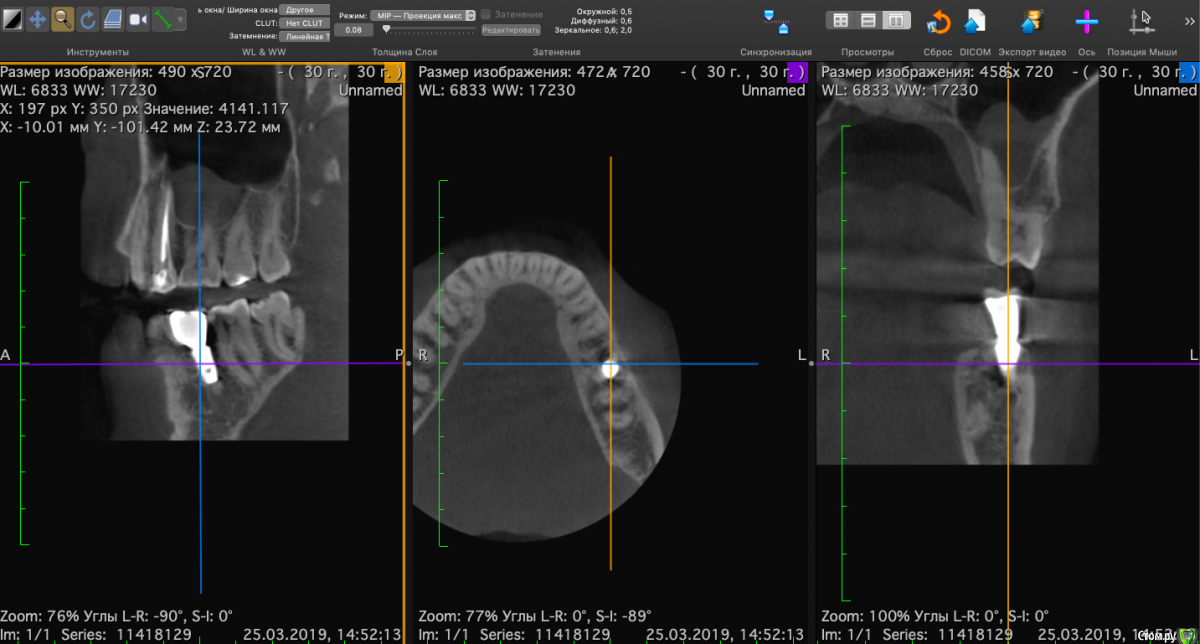

Nikitas Опубликовано 26 марта, 2019 Поделиться Опубликовано 26 марта, 2019 Восемь месяцев назад удален 36 зуб (на верхушках обоих корней был периодонтит), и одномоментно установлен имплантат. Полости, в которых было воспаление были заполнены графтом. На снимках КТ вокруг имплантата видны "полости", похоже что костной ткани в них нет. Уважаемые доктора, оцените пожалуйста, насколько такая степень приживления имплантата спустя 8 месяцев удачна, и каков прогноз? Будут ли эти полости зарастать костной тканью и насколько большая вероятность, что в них попадет инфекция? Насколько существенно, что имплантат установлен немного под наклоном? Субъективно жалоб нет. Ссылка на комментарий

Neilrus Опубликовано 26 марта, 2019 Поделиться Опубликовано 26 марта, 2019 чернота которую вы принимаете за пустоту - это шум от металла.Если вас ничего не беспокоит, то живите спокойно )наклон не беда. Ссылка на комментарий